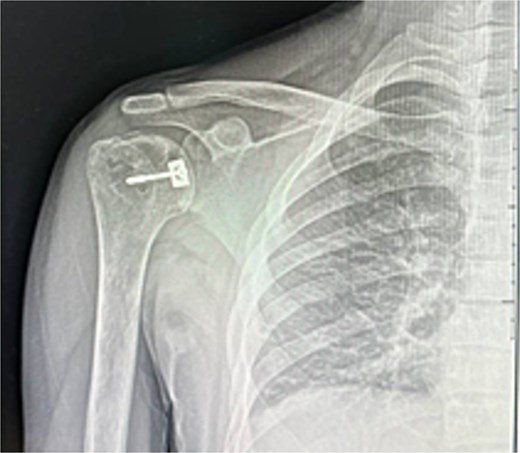

A 31-year-old male with sickle cell disease presented to the emergency department after an electrical shock caused him to fall onto the back of his shoulder. He developed severe pain and inability to use his arm. Examination revealed the shoulder in adduction and internal rotation with marked limitation of flexion and external rotation. X-rays showed posterior shoulder dislocation with a non-displaced proximal humerus fracture (Fig. 1). The injury was overlooked, and he was discharged in an arm sling.

He was counseled for open reduction and modified McLaughlin procedure. Through a deltopectoral approach, open reduction was achieved, and subscapularis with lesser tuberosity was transferred to the defect and fixed with a partially threaded screw. Postoperative X-rays showed satisfactory reduction (Fig. 3). He was discharged the next day in an external rotation brace.